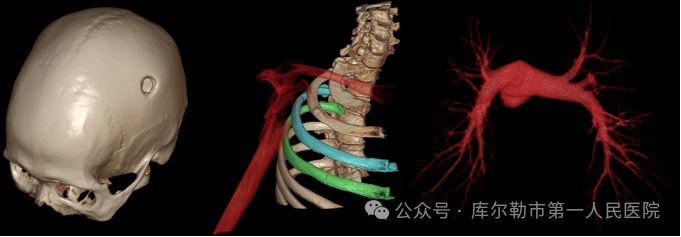

3、微剂量体检筛查-解除您的后顾之忧

采用源头低千伏成像模式,超高端320排CT可实现肺部、冠脉等全身各部位大扫描通量、微辐射剂量的体检筛查。低千伏扫描模式可以有效降低辐射剂量和对比剂用量,降低肾功能不全受检者增强检查风险,系统还可根据不同患者体型和扫描协议自动推荐扫描管电压,在降低患者扫描剂量的同时,优化对比度噪声比。

4、全速急诊扫描-抢救生命争分夺秒

针对胸痛、脑出血、外伤、急腹症等多种急诊检查场景,超高端320排提供全速急诊方案,检查时间最短化,图像评估直观化, 为抢救生命争分夺秒。AI 3D天眼导航系统可以自动识别全体位19个结构点以及业内最多的8种体位,快速智能完成扫描前准备工作,提高扫描效率,缩短急诊扫描时间。

开展常规CT及各种特殊影像检查:冠状动脉血管成像,胸痛三联成像,CT双肾、输尿管、膀胱成像,下肢动脉成像,头颈血管及四肢血管成像,骨关节三维重建成像;